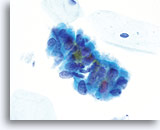

Adenocarcinoma in situ

Endocervical cells presenting in a strip with pronounced nuclear crowding. Biopsy – AIS – 60x